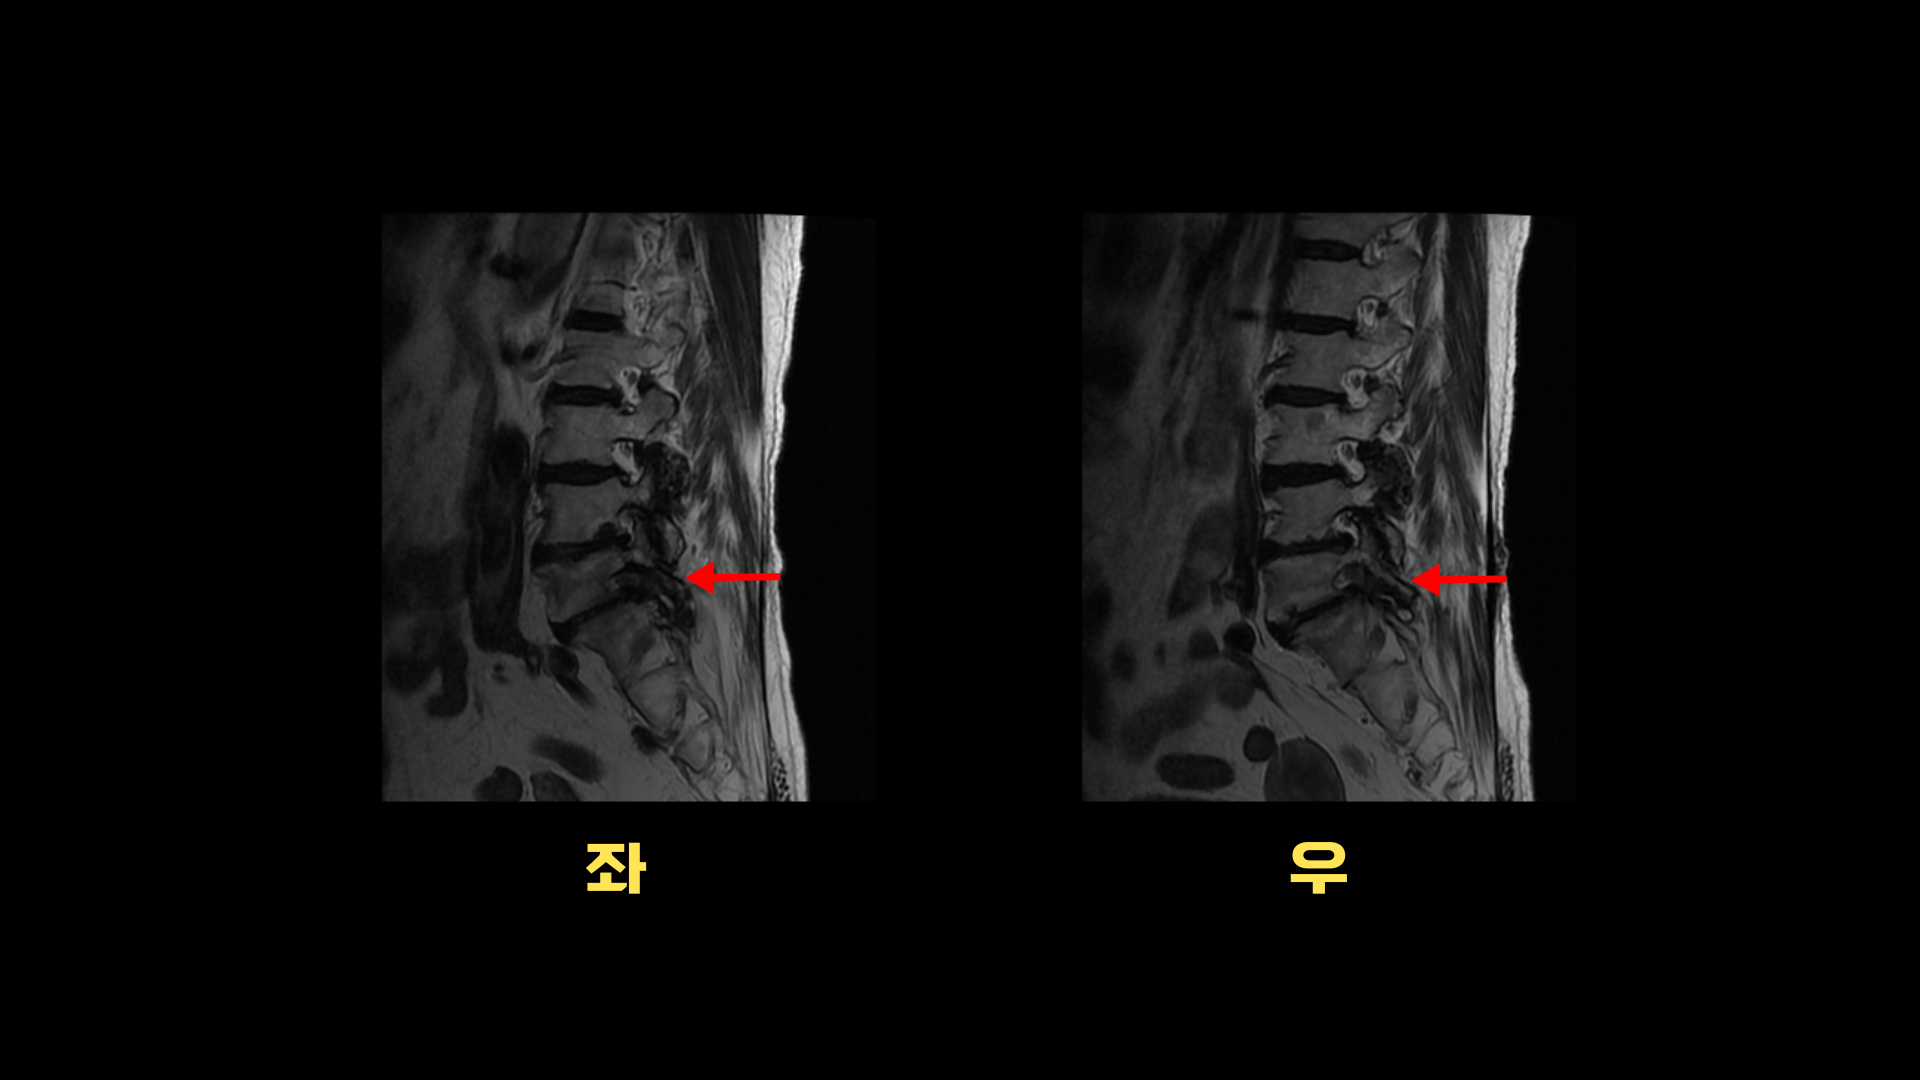

이분 MRI를 보면 퇴행성디스크가 여러 마디가 있고 그 중에서도 특히 5번 1번에는

전방전위증과 함께 2번의 수술로 인해 척추관 내부가 지저분해 보이고

또 오른쪽과 왼쪽으로 나가는 신경 구멍이 많이 좁아져 있습니다.